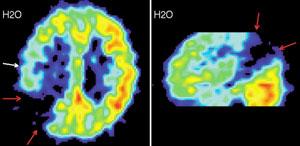

Именно наличие клиники во многом определяет возможности фундаментальных и прикладных исследований ИМЧ. Поэтому прежде всего несколько слов о ней. У нас прекрасные высококвалифицированные доктора и медсестры. Без этого нельзя: ведь мы на переднем крае, и нужна высочайшая квалификация, чтобы выполнять нерутинное, новое. У нас выполняются практически все стандартные манипуляции и наряду с ними и хирургическое лечение эпилепсии и паркинсонизма, проводятся психохирургические операции, в том числе и хирургическое лечение обусловленного героином обсессивно-компульсивного синдрома, знаменитая «пересадка мозга», точнее имплантация фетальной мозговой ткани, лечение магнитости-муляцией мозга, лечение афазии с помощью электростимуляции и многое другое. Накоплен десятилетний опыт клинических обследований с помощью позитронно-эмиссионной томографии. На рисунках приведена малая толика того, что может диагносцировать этот метод томографии. У нас лежат тяжелые больные, и мы стараемся помочь с помощью вышеперечисленных методов даже тогда, когда все остальные попытки были неудачны. Конечно, это удается не всегда. Но безграничных гарантий в лечении людей дать невозможно, а если кто-то дает их, это всегда вызывает очень серьезные сомнения.

Вообще, благодаря технике позитронно-эмиссионнной томографии (или сокращенно ПЭТ), стало возможно детальное изучение одновремено всех областей мозга, отвечающих за сложные “человеческие” функции мозга. Суть метода состоит в том, что малое количество изотопа вводят в вещество, участвующее в химических превращениях внутри клеток мозга, а затем наблюдают, как меняется распределение этого вещества в интересующей нас области мозга. Если к этой области усиливается приток глюкозы с радиоактивной меткой - значит, увеличился обмен веществ, что говорит об усиленной работе нервных клеток на этом участке мозга.

А теперь представьте, что человек выполняет какое-то сложное задание, требующее от него знания правил орфографии или логического мышления. При этом у него наиболее активно работают нервные клетки в области мозга, “ответственной” именно за эти навыки. Усиление работы нервных клеток можно зарегистрировать с помощью ПЭТ косвенно, по увеличению локального кровотока в активированной зоне. (Более ста лет назад было показано, что усиленная работа нервных клеток приводит к увеличению локального мозгового кровотока в этой области.)

Таким образом, удалось определить, какие области мозга “отвечают” за синтаксис, орфографию, смысл речи и за решение других задач. Мы предъявляем испытуемым различным образом организованные задания, при выполнении которых необходимо «задействовать» определенные свойства речи. Например, отдельные слова, предложения, связный текст. Сравнивая ПЭТ изображения, получаемые при этой деятельности, мы можем определить, где в мозге происходит обработка отдельного слова, где синтаксиса, а где смысла текста. Видны зоны, активирующиеся при предъявлении слов, неважно, надо ли было их читать или нет. Зоны, отвечающие за смысл текста, и другие. Интересно, и это будет рассмотрено ниже, что удалось обнаружить зоны, активирующиеся, чтобы «ничего не делать».